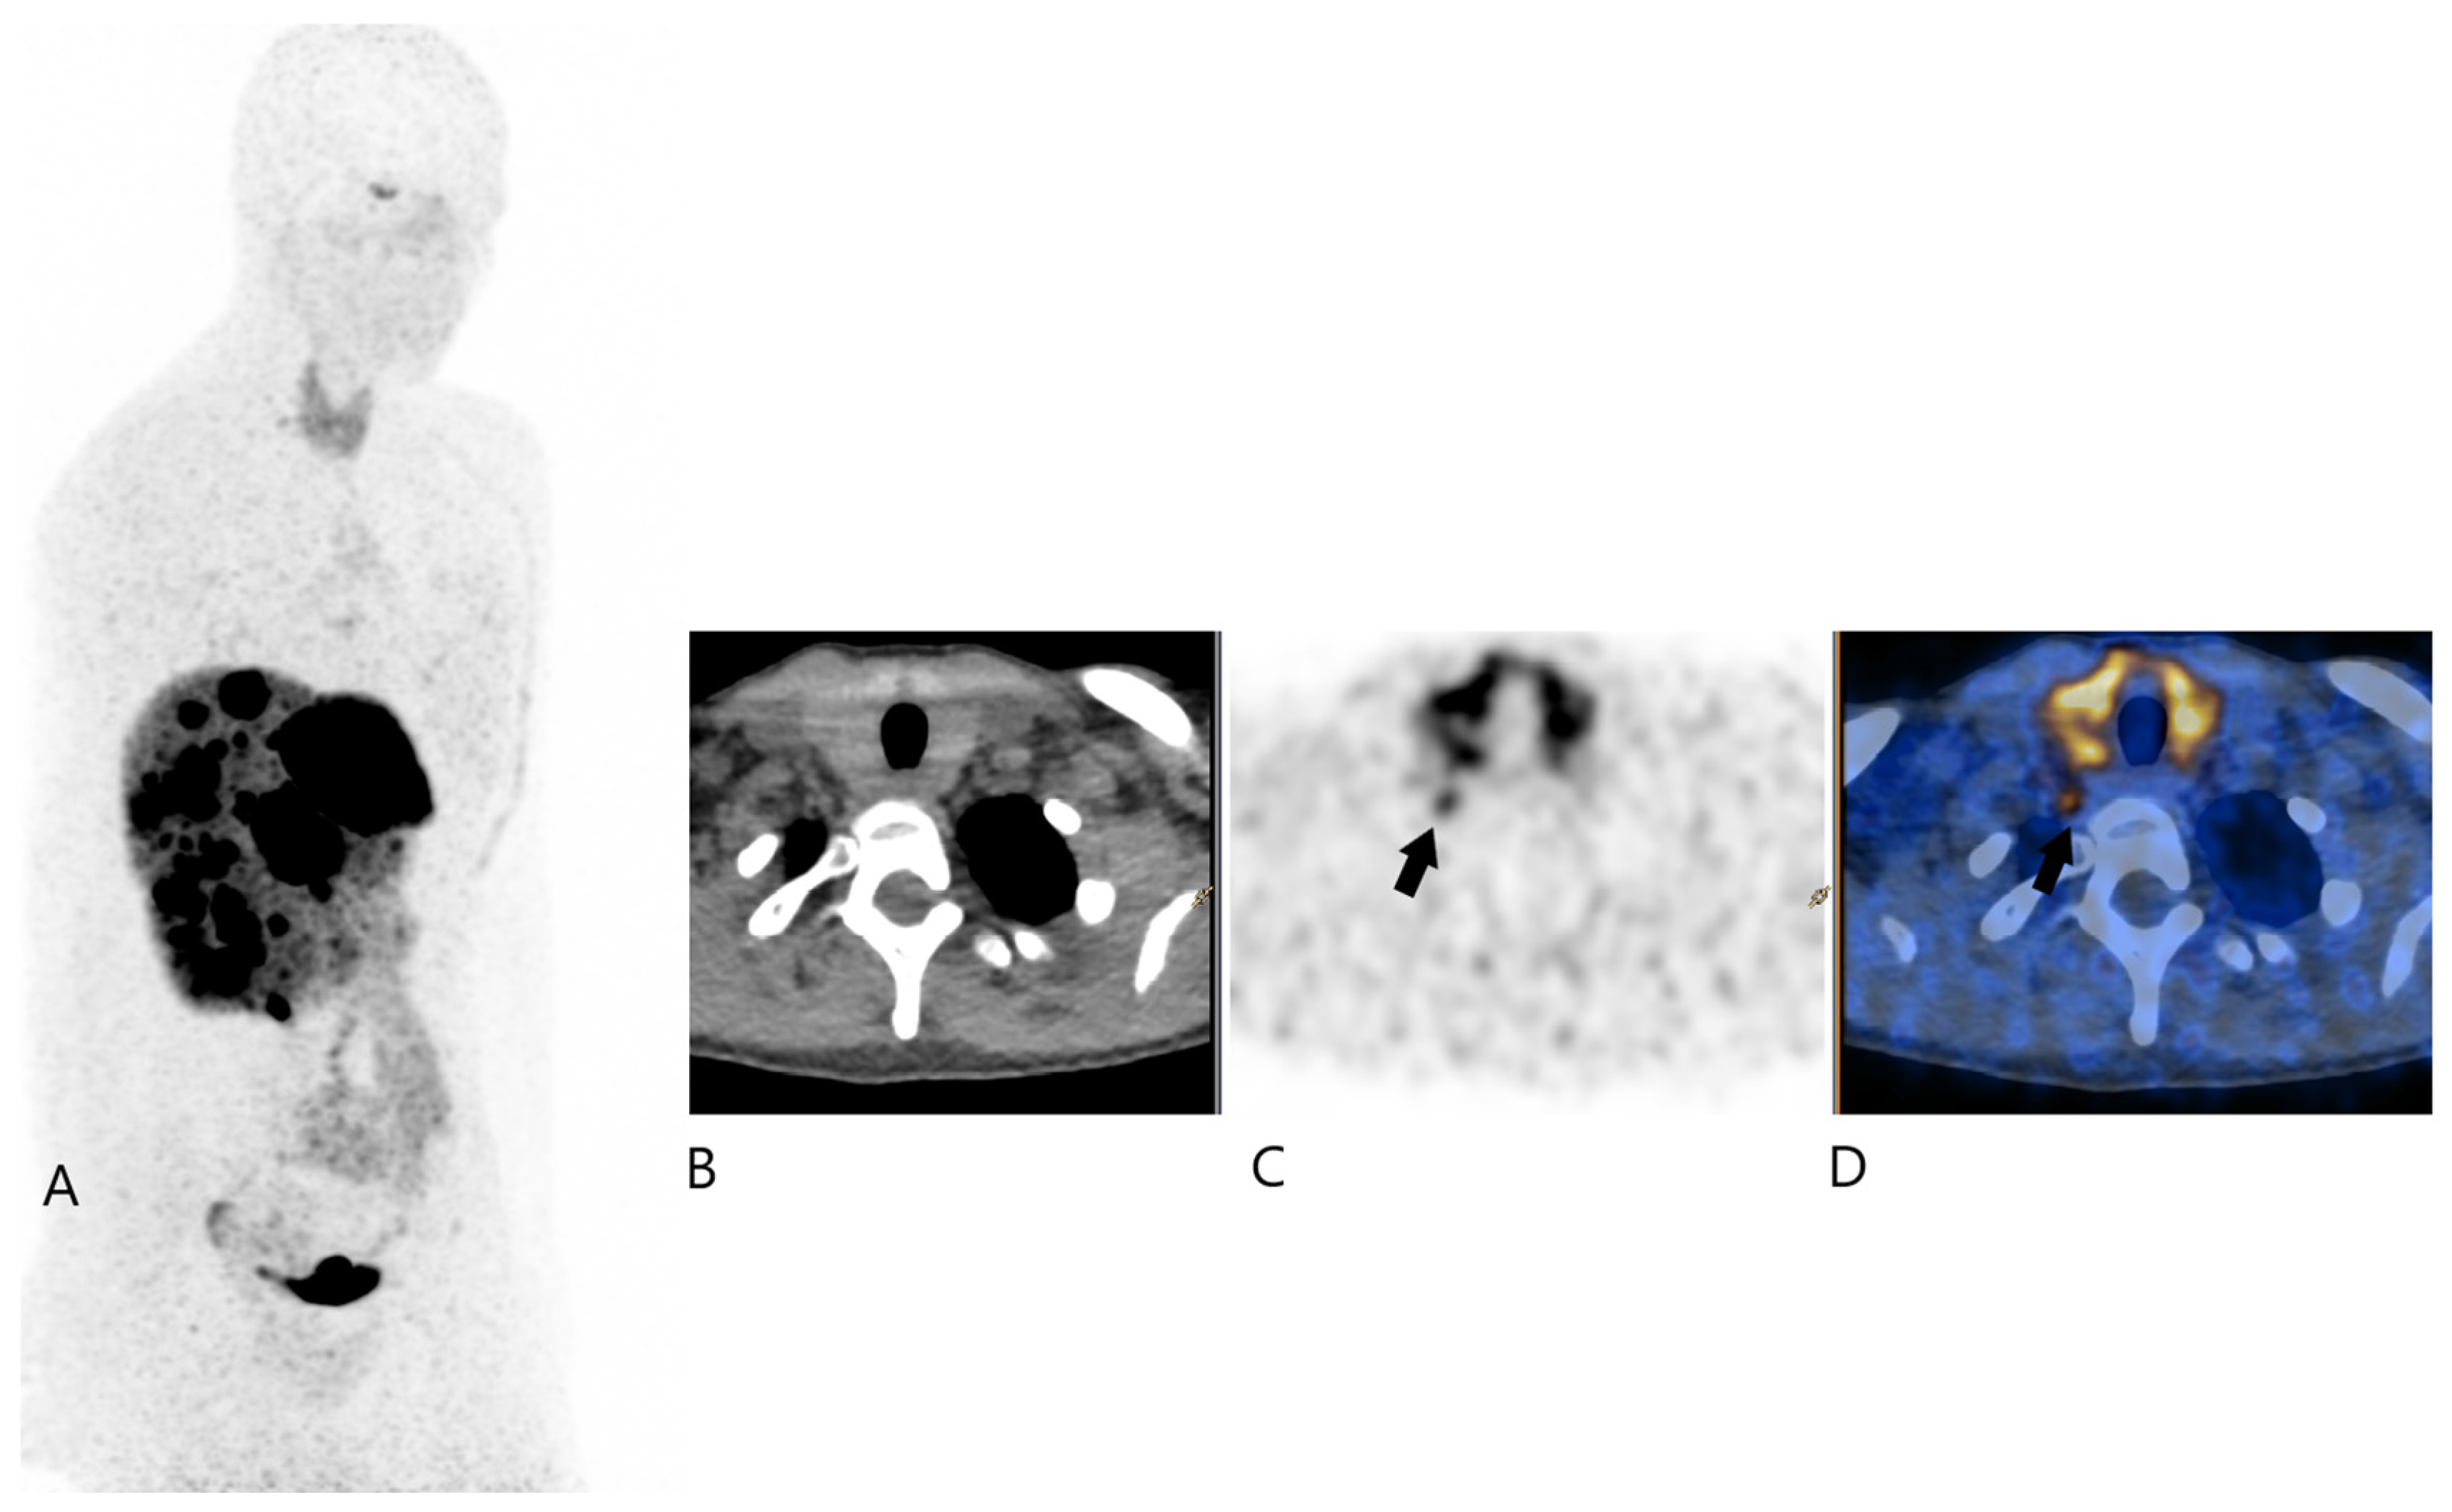

2. Case Report